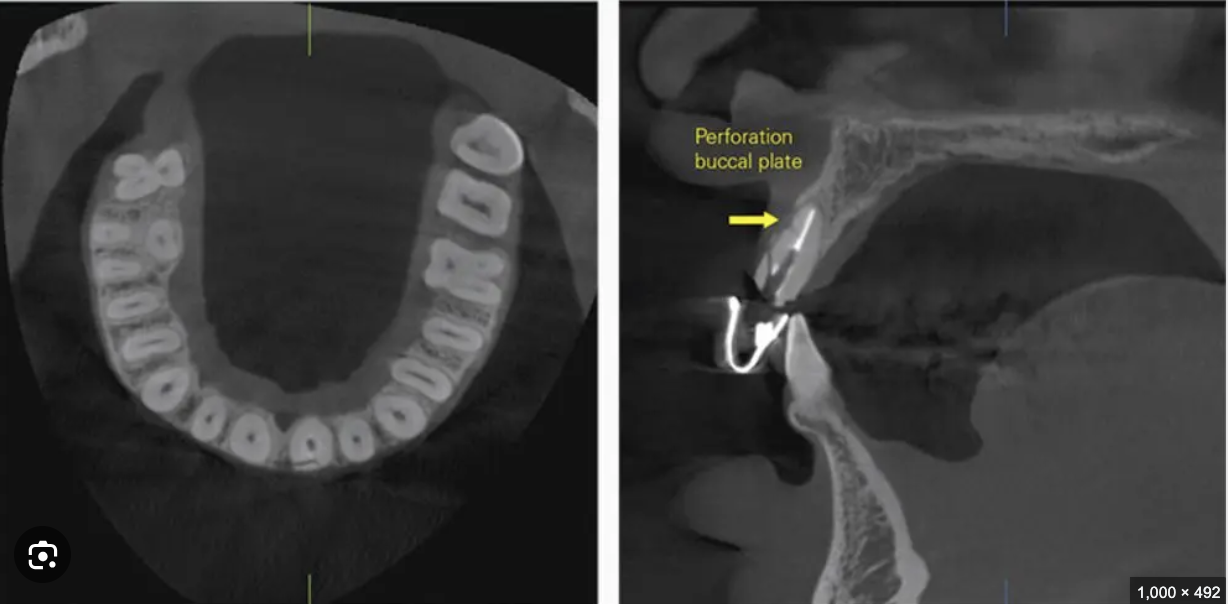

- Assessing treatment complications: Essential for detecting vertical root fractures, root perforations, and endodontic failures that may not be visible in conventional 2D radiographs.

- Perforations: Assess for iatrogenic perforations, their location, and their impact on periapical bone.